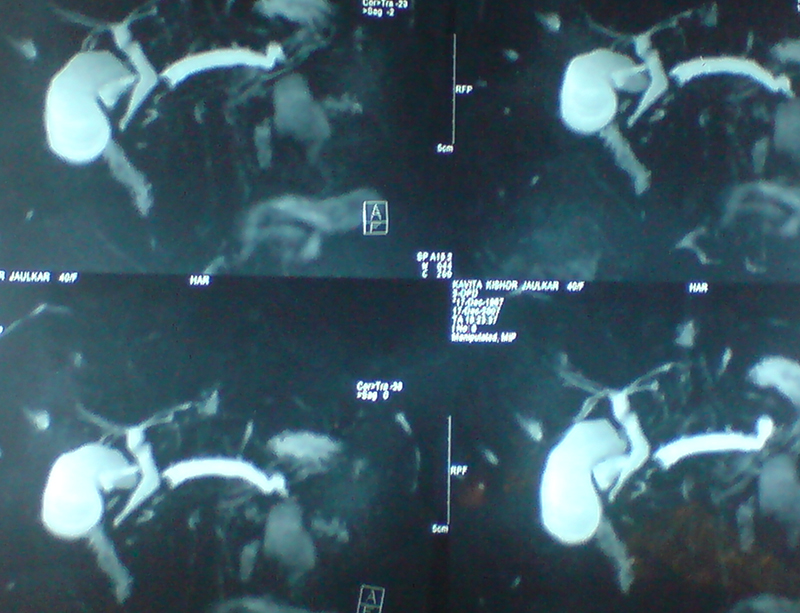

30 year old young lady with chronic pancreatitis, narrowing (stricture) of the pancreatic duct in the head and tail of pancreas and obstructing stone in the tail portion of the pancreatic duct presented to us with a recent attack of mild acute pancreatitis. She had undergone pancreatic duct stenting 3 times before this and stent migrated out of the duct at the last time following which she had acute pancreatitis. She was thoroughly evaluated with CT scan and MRI of abdomen. It showed that the duct had dilated irregularly in head and body of the pancreas and a stone was lodged in the tail. So she had disease both in the head and tail. She underwent a distal pancreatosplenectomy for the tail disease and a pancreaticojejunostomy (Head coring—Frey procedure) for the disease of the head and body of pancreas. She recovered well however the recovery was prolonged due to intra-abdominal infection caused by organisms in the infected pancreatic fluid. Infections originated from the pancreatic stents, were resistant to routine antibiotics and needed expensive drugs for infection control.